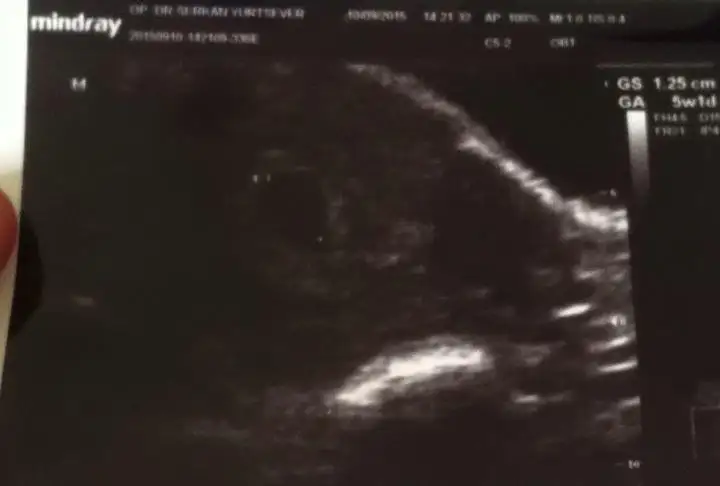

Kizlar bugün keseyi gördük SATA gore 6+1 im ama 5 haftalık dedi. Geç döllenme olabilir silinti yapma normal dedi. Çok şükür.. Allah saglikli bebekler versin hepimize

gözün aydın canım benim sat a göre 7+1 ama keseye göre 5+1 dedi doktor :)) hayırlısı inş. kese içinde bişi gözüktümü kese nin ölçüsünü söyledimi canım:)

canım benim 5+1 de bebiş görünmedi henüz 4 de görünmemesi bana görecok normal artık mecbur bekliycez birdaha nezaman gel dedi sana ? benim kese görüntüleri bak hiçbişi yok şimdilik daha :)

Kesenin ölçüsünü felan söylemedi canim. Şuan kese görünür sadece dedi. Elime verdiği ultrasyon goruntusundende biseye. anlamadim. Kaç günlük olduğu yazar dedi annem ama ben bisey göremedim. Doktora demedi

bak benimkinde 5w1d yazıyor oraya bak istersen belki yazıyordur canım